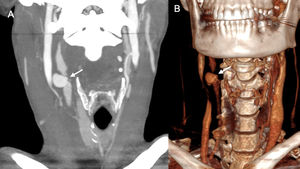

TraumaticVascular injuries can occur as a result of external trauma, whether blunt or penetrating, due to an accident, assault or other circumstances (Fig. 12). Minor blunt trauma can cause pseudoaneurysms in anticoagulated patients who are at increased risk of bleeding.21 In the extremities, most post-traumatic pseudoaneurysms are secondary to penetrating injuries and most commonly occur in the upper limbs.5,21

31-year-old woman who suffered an assault involving a penetrating stab wound with right submandibular entry and extensive accompanying bleeding requiring compression. Coronal maximum intensity projection (A) and 3D CT angiography reconstructions of the supra-aortic trunks in arterial phase showing a focal dilation of the right common carotid artery a few millimetres from its bifurcation, consistent with post-traumatic pseudoaneurysm.

Traumatic pseudoaneurysm of the superficial temporal artery is rare. It usually develops as a painless pulsatile mass in the temporal region, often following blunt or penetrating craniocerebral injury. The time of onset is variable and is influenced by the nature of the lesion; it can appear 2−6 h after the trauma or weeks later22 (Fig. 13).

86-year-old man presenting with craniocerebral injury one month prior and since then a pulsatile mass in the left frontotemporal region of about 3 cm in diameter (arrowhead) (A). The ultrasound scan (B) shows an oval image arising from the left temporal artery with a sac with mobile internal echoes and turbulent flow consistent with a pseudoaneurysm of the left temporal artery (arrow), partially thrombosed and with bidirectional flow on spectral Doppler. The pseudoaneurysm can also be seen in the sagittal maximum intensity projection reconstruction of baseline brain CT (C).